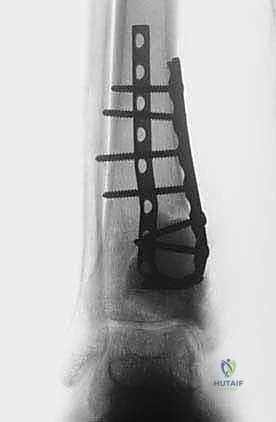

Intraoperative fluoroscopy and clinical images confirming the placement of robust internal fixation spanning the reconstructed defect.

Final radiographic verification of the reconstruction, demonstrating excellent alignment, hardware placement, and complete filling of the defect.

Despite meticulous technique, cryosurgical ablation carries a distinct and significant complication profile. As academic surgeons, we must counsel our patients transparently and be prepared to manage these complex sequelae. The most common and devastating complication is a postoperative pathological fracture. The incidence of fracture ranges from 5% to 15%, depending heavily on the anatomical location, the size of the cortical window, and the adequacy of prophylactic fixation. The profound thermal necrosis weakens the bone significantly, and the necrotic phase peaks between 4 to 8 weeks postoperatively, making this the highest-risk window for structural failure. Salvage management for a fracture typically involves revision open reduction and internal fixation (ORIF), often requiring longer spanning plates, structural allografts, or in severe cases of joint collapse, conversion to a megaprosthesis or total joint arthroplasty.